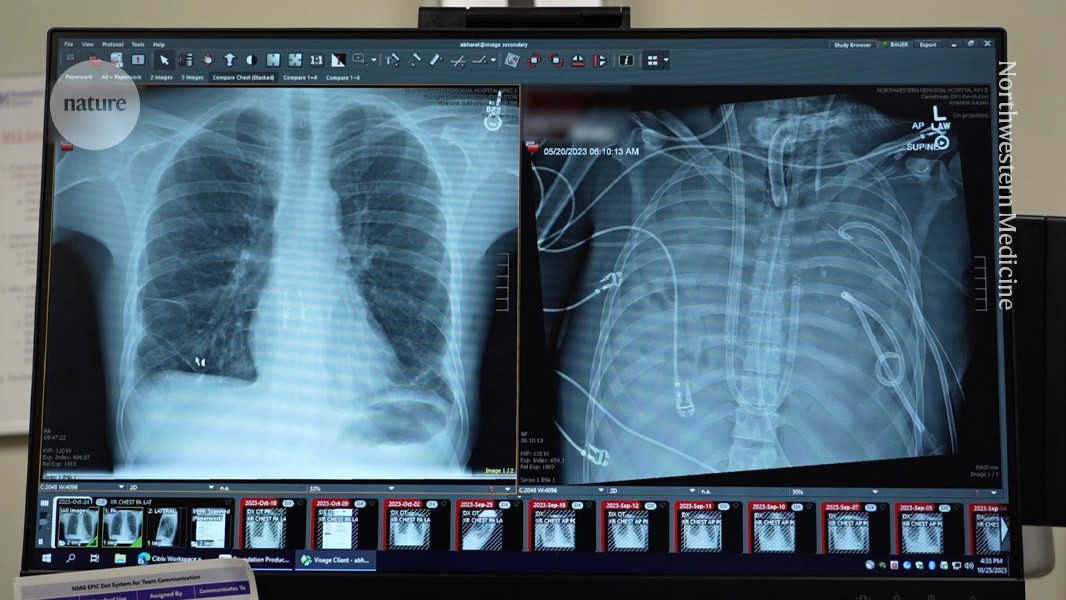

X-rays show a 33-year old patients’ new lungs (left) and old lungs (right).Credit: Northwestern Medicine A 33-year-old man survived for